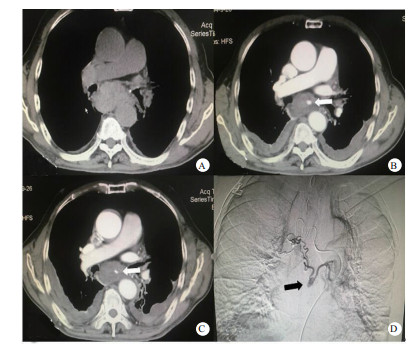

入院急诊心超示:升主动脉内径稍增宽。主动脉瓣反流(轻度)二尖瓣反流(轻度)。胸片示:右肺中叶感染性病变可能大,查胸部CT(图 1A)示:胸段食管不规则增厚,周边可见肿大淋巴结,建议胃镜及增强CT进一步检查。慢性支气管炎、肺气肿伴两肺感染,左肺支气管扩张,双侧少量胸腔积液。急诊医师予抗感染,化痰及减轻胃酸分泌等治疗后,患者胸痛未见好转,进一步查增强CT(图 1B)示:食管壁弥漫性水肿,围绕食管壁周围高密度影,考虑纵隔血肿形成,伴有活动性出血,联系介入科后行介入治疗,造影(图 1C)示:左右支气管动脉可见交通支,交通支可见假性动脉瘤表现,予行超选择性靶血管栓塞术。术后3 d复查胸部增强CT(图 1D)示:支气管动脉瘤破裂出血介入栓塞术后,纵隔血肿。较前纵隔血肿稍有吸收,目前未见活动性出血征象。患者术后第6天好转出院。

| 图 1 患者影像学检查结果(A:患者入院后胸部CT检查结果; B:患者胸部增强CT结果,箭头所指处为支气管动脉瘤显影; C:患者术后复查增强CT结果,箭头所指处为动脉瘤已栓塞; D:患者造影中结果,箭头所指即左右支气管动脉交通支中的动脉瘤) |